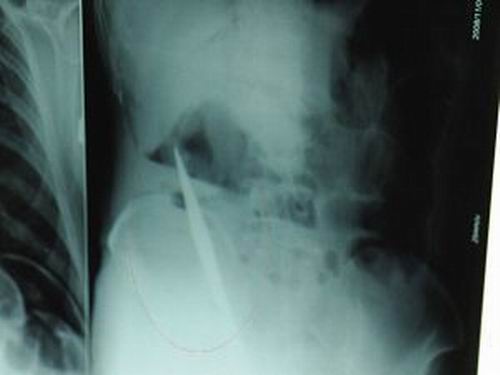

X光片上,尖刀清晰可見。

從男子體內(nèi)取出的尖刀足足有19厘米長。

江蘇銅山一58歲男子因服毒被送到醫(yī)院搶救,可醫(yī)生采取搶救措施后卻發(fā)現(xiàn)效果不佳。后來經(jīng)細(xì)致檢查,醫(yī)生有了個驚人的發(fā)現(xiàn),該男子的體內(nèi)竟然有一把尖刀,醫(yī)生通過手術(shù)將位于其腹部右側(cè)橫結(jié)腸下緣的尖刀取了出來。這把尖刀足足有19厘米長!據(jù)醫(yī)生推測,這把刀應(yīng)該是從肛門推進(jìn)體內(nèi)的,不知男子為何想以如此殘酷的方式結(jié)束自己生命。由于搶救及時,該男子已暫時脫離危險。

昨天(11月6日)上午,記者在徐州礦務(wù)集團(tuán)總醫(yī)院重癥監(jiān)護(hù)室見到了這名男子,目前他雖然已經(jīng)恢復(fù)了意識,但還不能開口說話,需要呼吸機輔助呼吸。據(jù)醫(yī)生介紹,4日中午12時左右,這名男子因服毒輕生被緊急送到醫(yī)院進(jìn)行搶救,之前,這名男子已經(jīng)在當(dāng)?shù)剜l(xiāng)鎮(zhèn)醫(yī)院進(jìn)行了近20小時的治療,但效果不佳!安∪吮晦D(zhuǎn)院到礦總院時已神志不清,血壓極低,處于休克狀態(tài)!本茸o(hù)人員給男子洗胃、初步處理以后,發(fā)現(xiàn)男子呼吸急促,于是趕緊給他拍片檢查。結(jié)果讓所有的醫(yī)生大吃一驚,竟有一把尖狀異物橫在該男子腹腔內(nèi)!當(dāng)天下午5時30分,輕生男子被推上了手術(shù)臺。經(jīng)過40多分鐘的手術(shù),該男子腹腔被打開,手術(shù)醫(yī)生發(fā)現(xiàn),男子體內(nèi)的金屬狀異物竟然是一把長19厘米的尖刀!